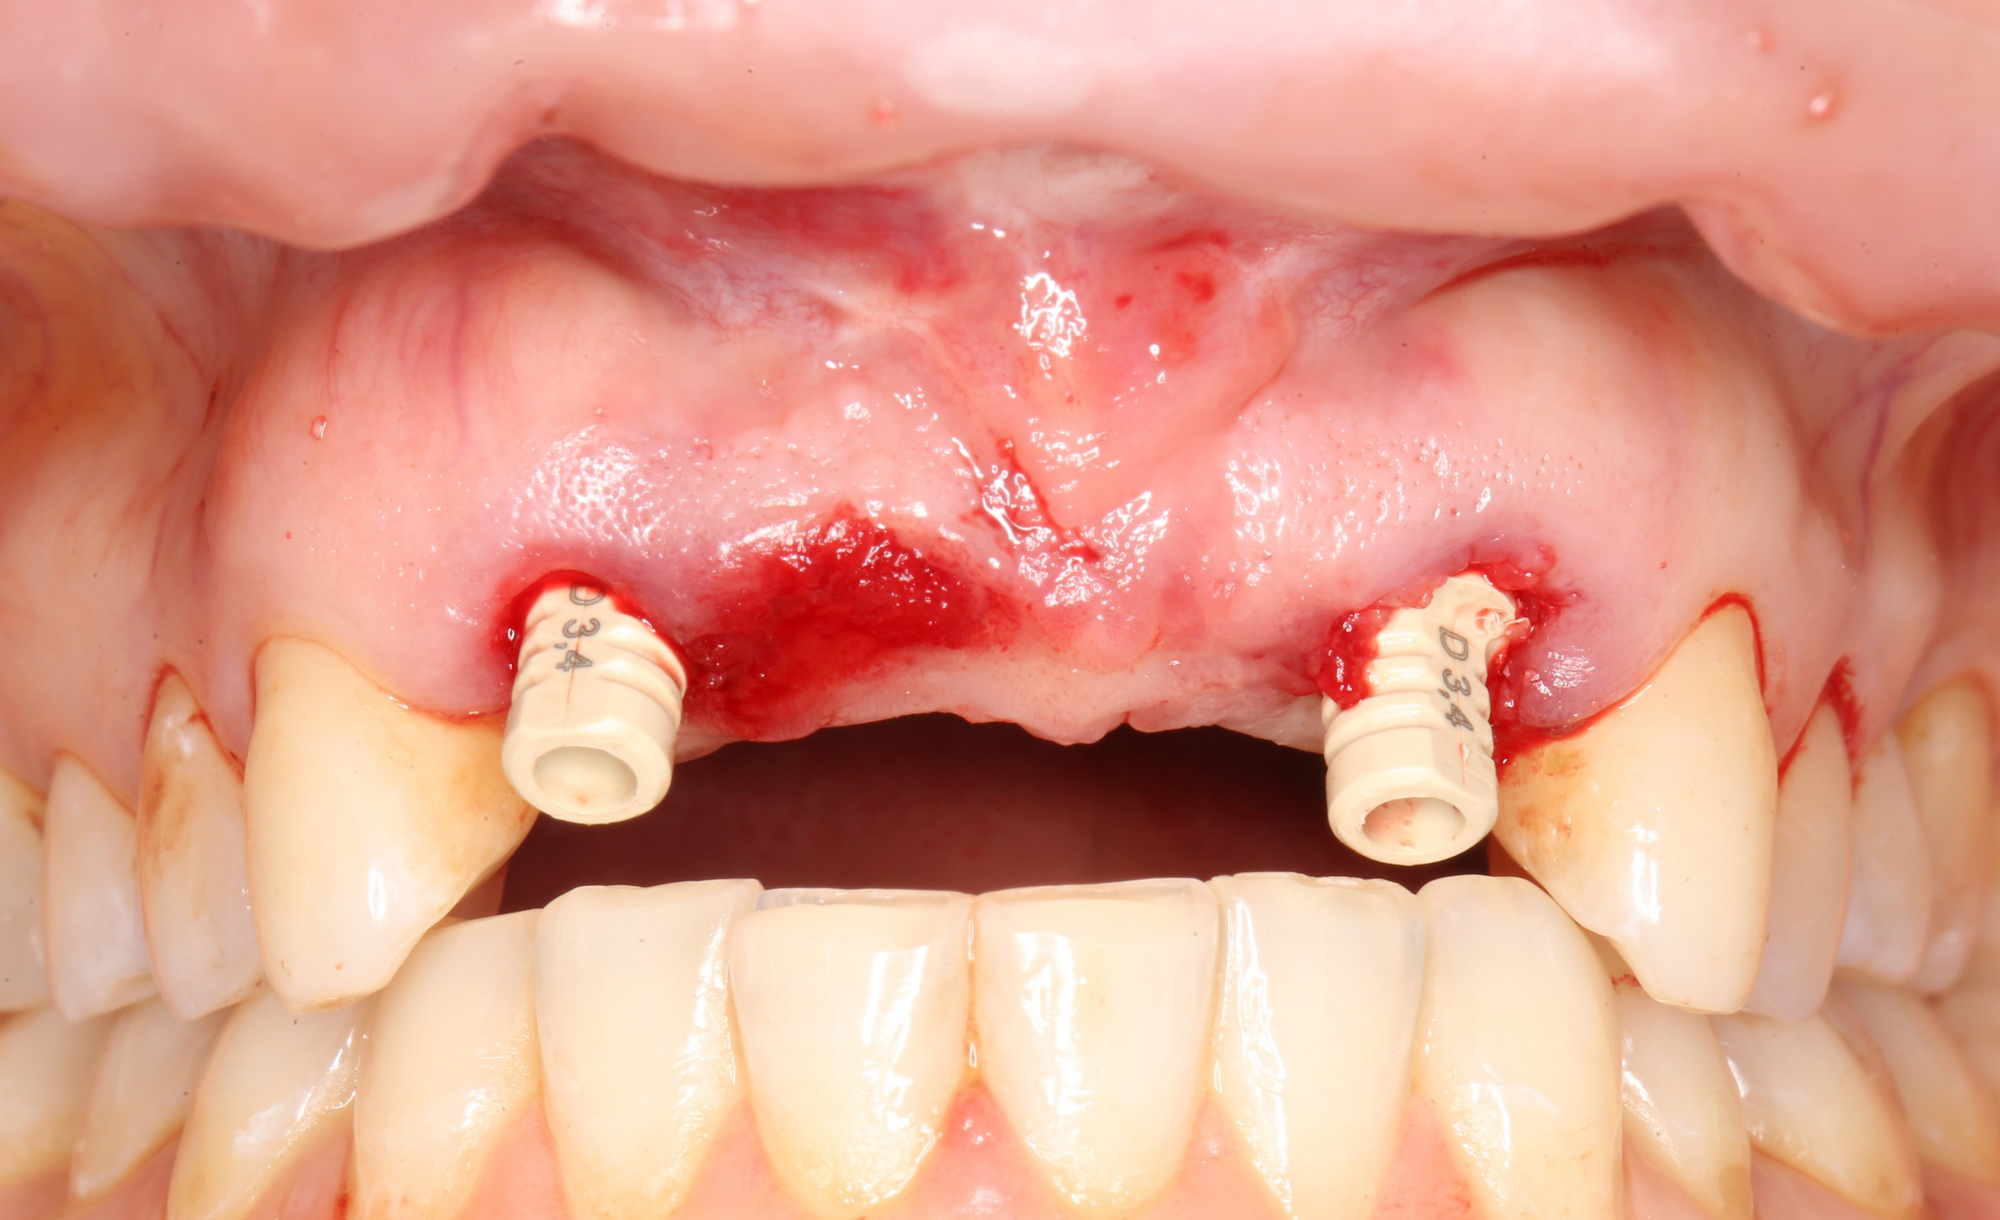

Таким образом, мы устанавливаем оба имплантата:

Наш физиодиспенсер позволяет измерять крутящий момент при установке — у нас получилось среднее значение около 20 Нсм. Этого достаточно для немедленного протезирования.

Но прежде, чем мы к нему перейдём, еще раз проверим положение имплантатов:

Поскольку мы планируем в качестве временных использовать абатменты Esthetic Cap, необходимо правильно ориентировать имплантаты по граням внутреннего шестигранника. Это несложно сделать по имплантоводу (на нём есть насечки) или предустановленному абатменту TempBase.

Фиксируем Esthetic Cap на имплантаты. Усилие при установке — 14 Нсм (больше ключ Xive не позволяет):

Еще раз проверим позиционирование имплантатов:

Поскольку трансгингивальная часть временного абатмента Esthetic Cap полностью перекрывает апертуру лунки зуба, мы можем обойтись без швов. Вообще без швов.